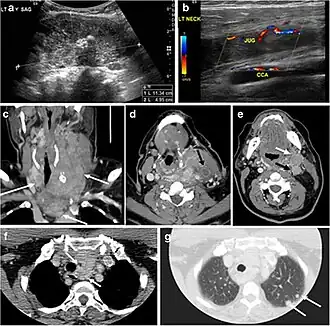

Fig. 4. A 45-year-old male patient presented with anterior mediastinal metastatic PTC lesions and occult primary on imaging. Histopathology examination of the resected thyroid gland revealed micro-foci of PTC; the largest, in the isthmus, measured 4 mm. a transverse greyscale ultrasound of the thyroid demonstrates homogeneous gland with normal echogenicity and size. No focal lesion or micro-calcifications. b Non-enhanced CT scan obtained as part of PET/CT examination shows a heterogeneous, large, relatively dense anterior mediastinal mass (white arrow) with peripheral calcification (arrowheads). Thyroid gland has normal CT appearance with no abnormal FDG uptake (not shown).[1] -

Fig. 6. A 61-year-old female patient with locally aggressive PTC. an Enhanced axial CT scan of the neck demonstrates a heterogeneous infiltrative thyroid mass. This mass diffusely involves the entire gland and circumferentially encases the trachea with involvement of bilateral tracheoesophageal grooves (white arrows). b, c Additional axial cranial images show right cricoid cartilage destruction (black arrows in b), right thyroid cartilage destruction (black arrow in c), right vocal cord paralysis (white arrows in b), and bilateral cervical lymphadenopathy (arrowheads).[1]

Finally, the possibility of metastatic disease should be excluded. PTCs and medullary thyroid carcinomas tend to metastasize to regional lymph nodes. According to the AJCC/UICC TNM staging system, the nodal stage is classified by site: N1a indicates level VI nodal involvement, including paratracheal nodes; N1b indicates unilateral or bilateral lateral cervical nodal disease or superior mediastinal nodal disease (Figs. 4, 55 and and6)6).[1]

Surgery is the primary mode of treatment for DTCs. Post total thyroidectomy radioactive iodine (RAI) ablation is an option, especially in patients with distant metastasis, tumours larger than 4 cm, or extra-thyroidal disease extension. Ultrasound examination is usually adequate in evaluating primary tumours and cervical lymph nodes. Preoperative cross-sectional imaging with CT or MRI is indicated if there is a concern for local invasion that may alter the patient's staging as well as surgical approach (Figs. 4, 55 and 6)6) . Some thyroid primaries may be small, diffuse, or multifocal and therefore may be occult on imaging (Fig. 4) .[1]